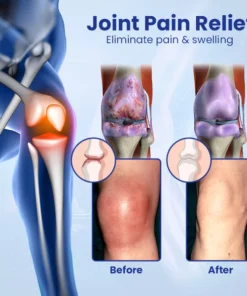

What causes joint pain?

Joint pain is caused by a variety of causes, including inflammatory joint disease, fractures and injuries, aging, infections, metabolic problems and lifestyle factors. These conditions lead to arthritis, joint pain and limited range of motion, which can negatively impact the quality of life of those affected that interfere with their ability to lead active and fulfilling lives.

Ceoerty™ JointRenew Bone Repair Gel Roller has been carefully designed to relieve joint discomfort, stiffness and inflammation. Its unique roll-on formula quickly penetrates the skin and delivers a blend of natural anti-inflammatory ingredients exactly where they are needed. This fast-acting blend provides rapid relief from joint discomfort and stiffness, allowing you to carry out your daily activities comfortably. Designed with precision, it aims to provide targeted relief for joint and bone pain by delivering a combination of organic ingredients directly to the area in need of relief.